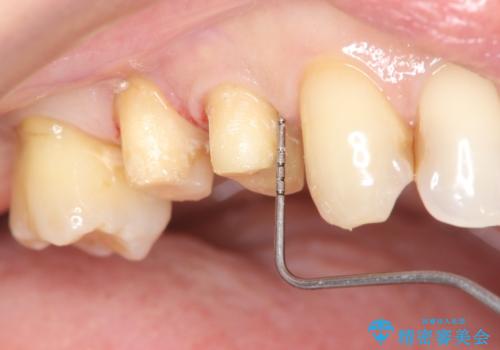

今回連結補綴を行うにあたり、歯周病の問題を解決するために再生療法・歯周ポケット除去手術を、またより歯の神経を保存し力に対抗できる環境を整えるために小矯正を行い精度の高いメタルボンドクラウンを製作することができました。